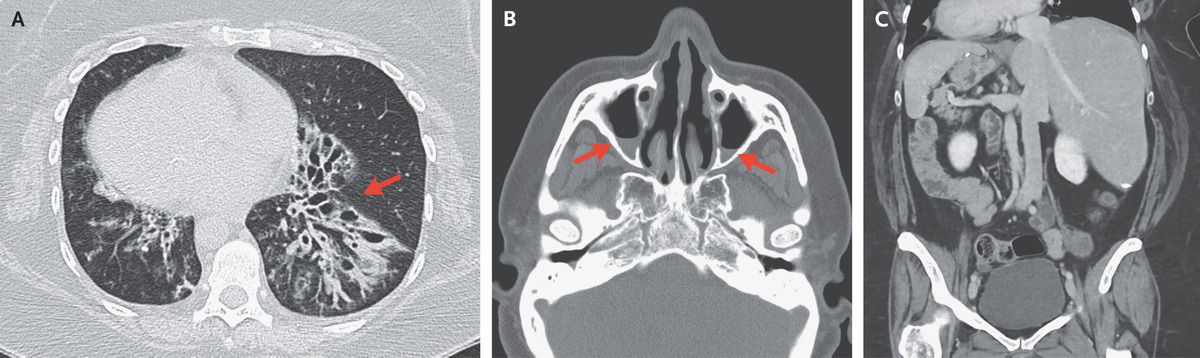

A 46-year-old woman with Kartagener’s syndrome presented to the primary care clinic with a 2-week history of fevers, worsening productive cough, and shortness of breath. In the clinic, she was afebrile and had an oxygen saturation of 95% while breathing ambient air. The examination was notable for rales and expiratory wheezing in both lungs. Computed tomography (CT) of the chest showed bronchiectasis in both lower lobes, with tree-in-bud nodularity. Bronchiectasis was most prominent in the lower left lobe (Panel A, arrow). Known dextrocardia was also noted. Sputum cultures grew Pseudomonas aeruginosa; treatment with levofloxacin was initiated, and the cough, shortness of breath, and fevers resolved. Two months later, facial pain developed, and CT of the head showed findings consistent with acute sinusitis with maxillary sinus air–fluid levels (Panel B, arrows), as well as chronic mucosal thickening. The patient’s symptoms again abated after antibiotic treatment. A previous abdominopelvic CT had shown situs inversus totalis (Panel C). Kartagener’s syndrome, a subtype of primary ciliary dyskinesia, is characterized by the triad of situs inversus, chronic sinusitis, and bronchiectasis. The syndrome is also associated with infertility. This patient continues to follow up with a multidisciplinary team.